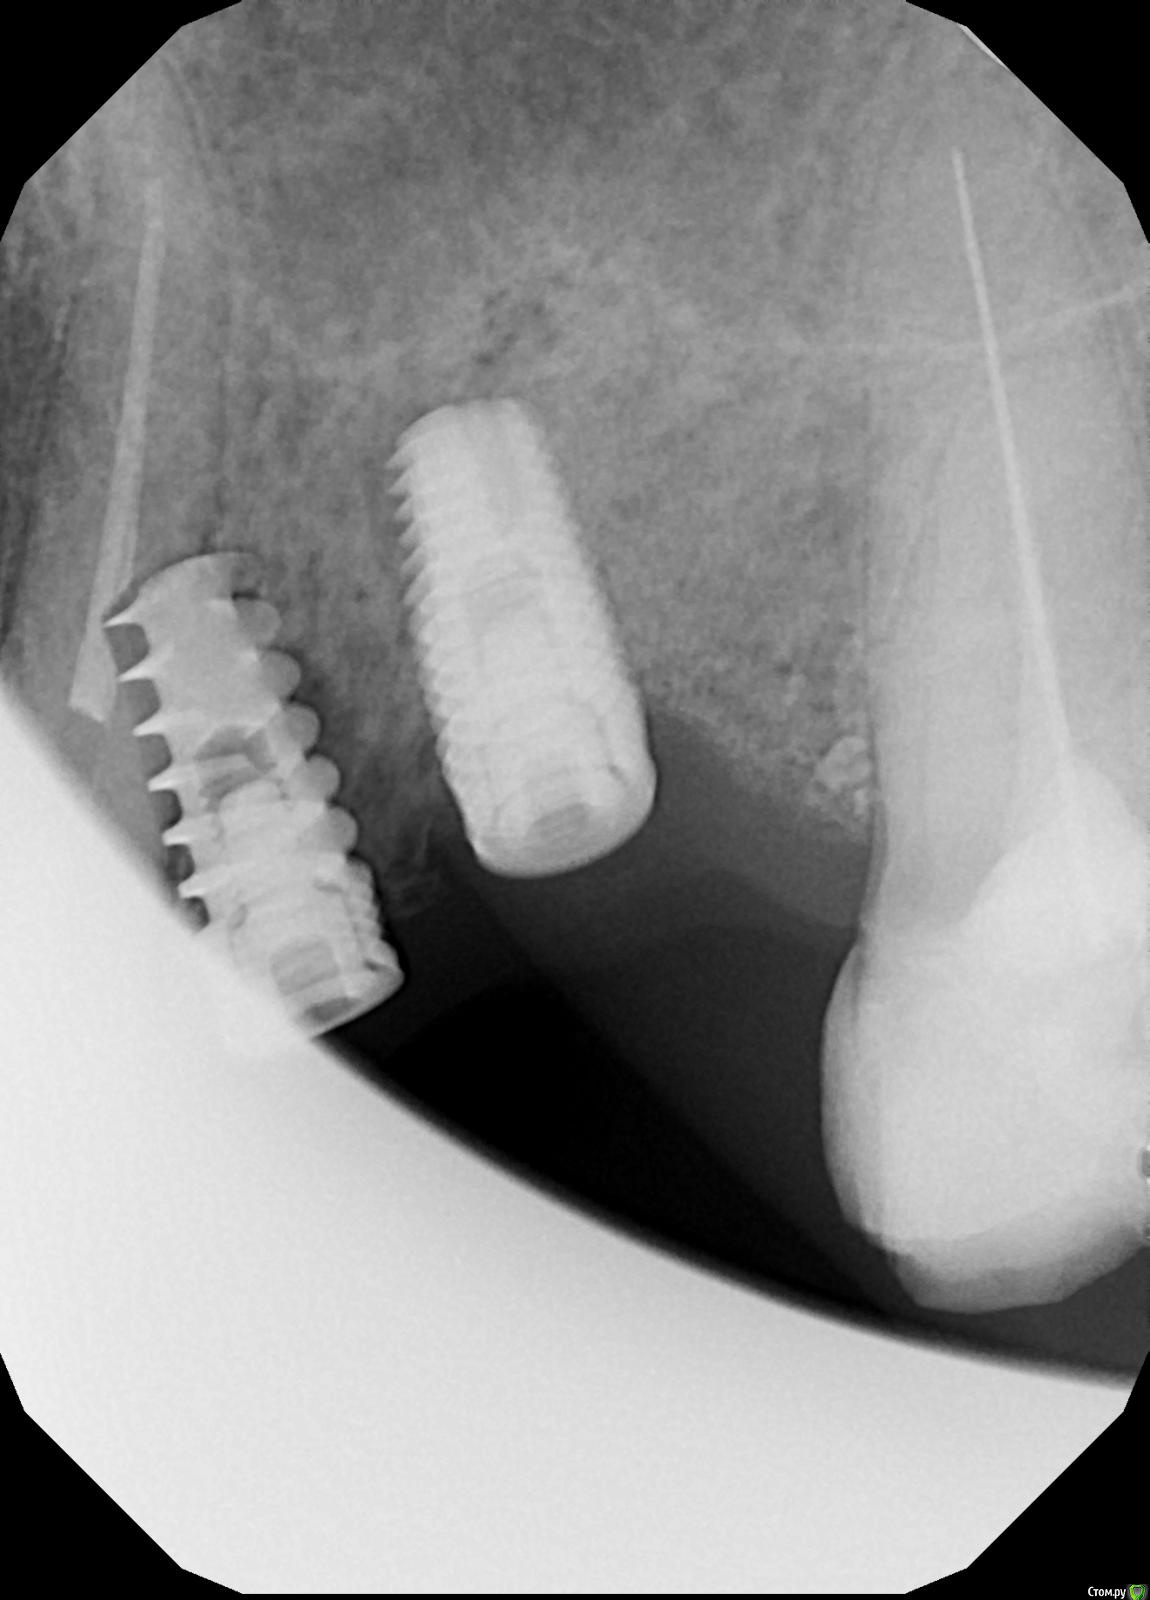

NazranDantist Опубликовано 5 июня, 2016 Поделиться Опубликовано 5 июня, 2016 Вот так поставили имплант. Кто что предложит делать? Если выкручивать, что делать с 23 зубом? Симпотоматики никакой, ничего не беспокоит. Ставили примерно в марте. Мне нужно протезировать. Может так оставить, если торк выдержит. А если не выдержит, опять возвращаемся к вопросу, что делать с 23 . На КТ думаю нет смысла отправлять, будет фонить металл. Ссылка на комментарий

4ebstom Опубликовано 5 июня, 2016 Поделиться Опубликовано 5 июня, 2016 Другой тоже не в идеальной позиции... 1 Ссылка на комментарий

vse32 Опубликовано 5 июня, 2016 Поделиться Опубликовано 5 июня, 2016 А в 26 серебряный штифт? Один на все каналы. Там похоже не один фэил. Ссылка на комментарий